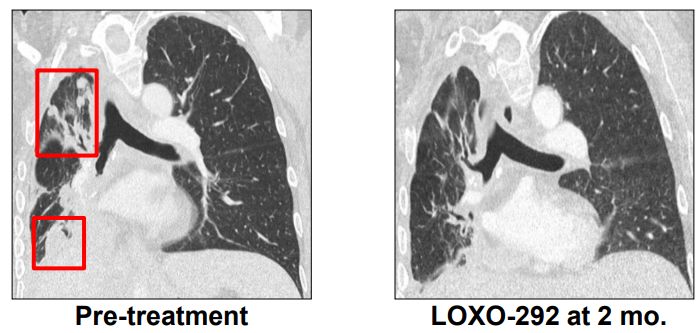

M女士走图无路的情况下接受了基因检测,发现了KIF5B-RET融合,开始接受600 mg BID靶向药 alectinib治疗(PR,7个月),由于脑转移进展增加至900mg BID,后脑转移症状严重,M女士接受了LOXO-292治疗,于是奇迹出现了,治疗两个月后,M女士肺部的病灶明显好转,脑部病灶几乎全部消失!